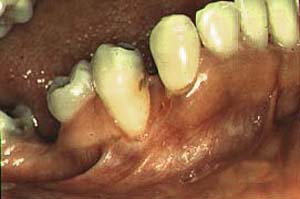

Secuestro óseo |